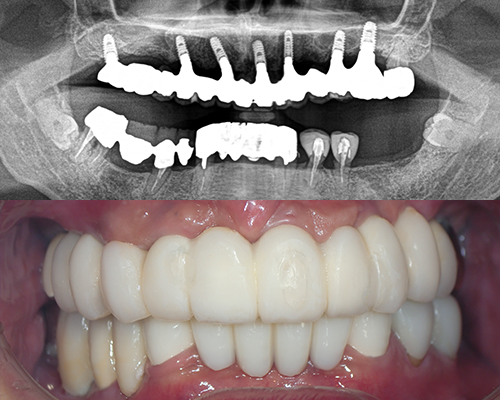

| 施術内容 | 右下奥歯3本欠損。入れ歯を使っていたが金具が折れて数年使っていない。金具のない目立たない入れ歯を希望していたが、固定式で安定したインプラント治療へ。インプラントは2本、冠は3本ブリッジ。 |

|---|---|

| 治療期間 | 4ヶ月 |

| 治療費 | 約68万円(チタンブリッジ) |

| 副作用・リスク | インプラント治療は手術を伴います。腫れや痛みが少なくなるよう努力をしておりますが、多少の腫れや痛みが出ます。しかし、痛み止めで抑えられる程度ですのでご安心ください。 |

※表示は全て税込表示です。